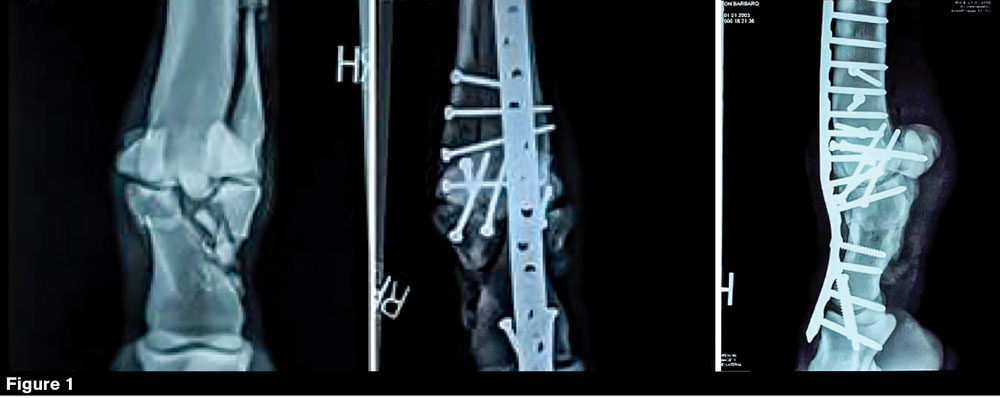

Stumbling out of the starting gate at Pimlico Race Course on May 20, he fractured three bones in and around the fetlock of his right hind leg. The very next day, he arrived at the University of Pennsylvania’s New Bolton Center where equine surgeon Dean W. Richardson reconstructed the limb. Equine veterinarian Andrew van Eps remembers the day vividly. He was working on another horse that had been brought in with a critical condition when Barbaro arrived.

“Barbaro had a terrible hind limb fracture,” he says. “The expertise, the equipment and the facilities for recovery that these horses have make it quite possible to fix complex fractures.”